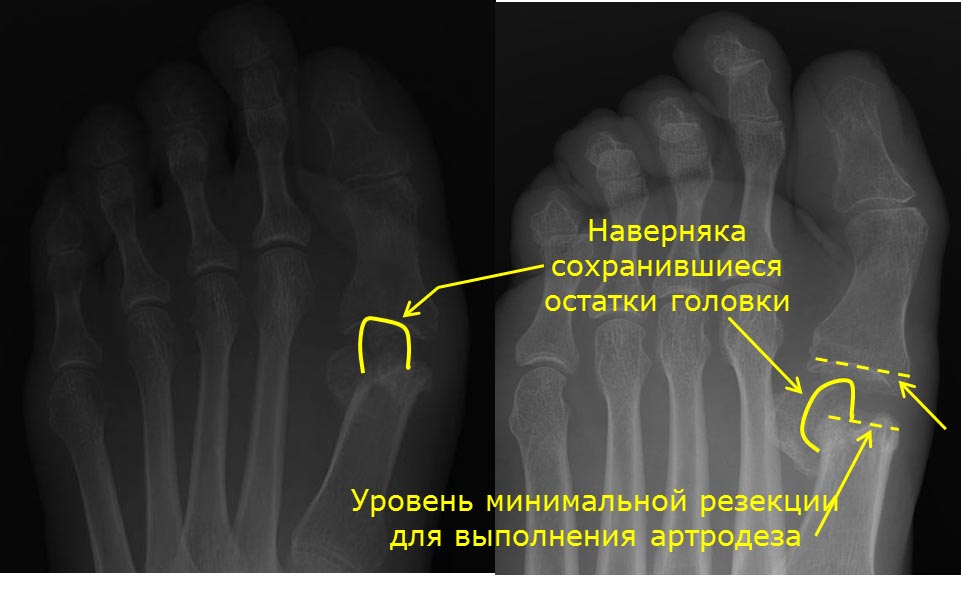

Причина центральной метатарзалгии в данном случае очень понятна, так же как и то, что нужно делать по этому поводу: любые укорачивающие и поднимающие головки М2-3 (4?) остеотомии. Но автор поста написал о болях в суставе большого пальца. Для меня причина этой боли непонятна. Соответственно, и что делать по данному поводу неясно. Говорить, что у пациентки полностью отсутствует головка М1 мы не можем. Во вложении я обрисовал то, что точно осталось от головки.

Но в каком положении находится этот фрагмент и насколько он велик, и есть ли еще остатки головки, без рентгенограммы в боковой проекции или КТ я не знаю. Предположим, что будет выполнен артродез. Если для его выполнения резецировать остатки головки, то при таком большом расстоянии между М1 и основной фалангой, как сейчас, даже установка между артродезируемыми поверхностями трансплантата толщиной 1 см приведет к еще большему укорочению первого луча. Избавит ли такой артродез пациентку от болей? Очень сомневаюсь. Потому что не понимаю, чем анкилоз ПФС1 будет лучше представленного на снимках состояния. К сожалению, без дополнительной информации дальнейшее обсуждение данного случая потеряло смысл.